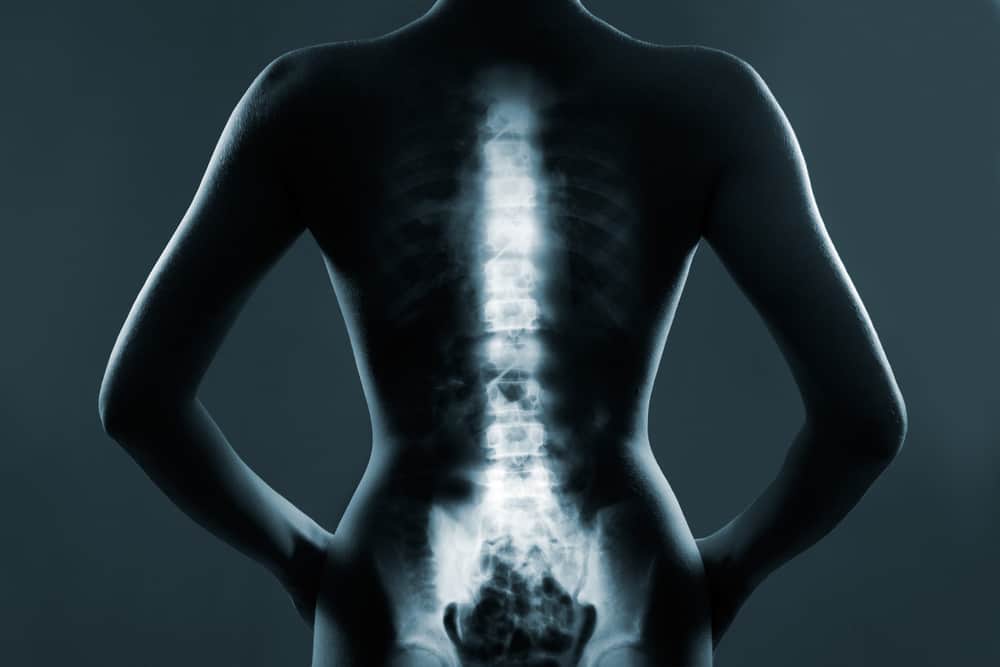

घायल डिस्क की वजह से दर्द हो सकता है। डिस्कोग्राम एक एक्स-रे प्रक्रिया है जो यह निर्धारित करने के लिए किया जाता है कि कोई विशेष डिस्क दर्द का कारण है। डिस्कोग्राम उत्तेजक परीक्षण है जो दर्द को खत्म करने की बजाय फिर से उत्पन्न करता है। डिस्कोग्राम के दौरान दर्द उत्पन्न होने से डॉक्टर को यह निर्धारित करने में मदद मिलती है कि दर्द का कारण किसी विशेष डिस्क में लगी चोट है या नहीं।

परीक्षण टेबल पर आपको पेट के बल या करवट लेकर लेटना होगा। आपकी स्किन साफ करने के बाद डॉक्टर सुन्न करने के लिए इंजेक्शन देगा ताकि डिस्कोग्राम के दौरान सुई लगाने से दर्द महसूस न हो। डॉक्टर शरीर के अंदर सुई की स्थिति का पता लगाने के लिए इमेजिंग तकनीक (फ्लोरोस्कोपी) का इस्तेमाल करता है। फ्लोरोस्कोपी सुई को सुरक्षित व सटीक तरीके से डिस्क के बीच में जांच के लिए पहुंचने में मदद करता है। इसके बाद डिस्क में कॉन्ट्रास्ट डाई इंजेक्ट की जाती है और एक एक्स-रे या सीटी स्कैन की मदद से यह देखा जाता है कि डाई फैली या नहीं।

यदि डाई डिस्क के केंद्र में रहती है तो इसका मतलब है कि डिस्क सामान्य है। यदि डाई डिस्क के केंद्र से बाहर फैल जाती है तो इसका मतलब है कि डिस्क में कुछ बदलाव हुए हैं। यह बदलाव दर्द का कारण हो भी सकते हैं और नहीं भी।